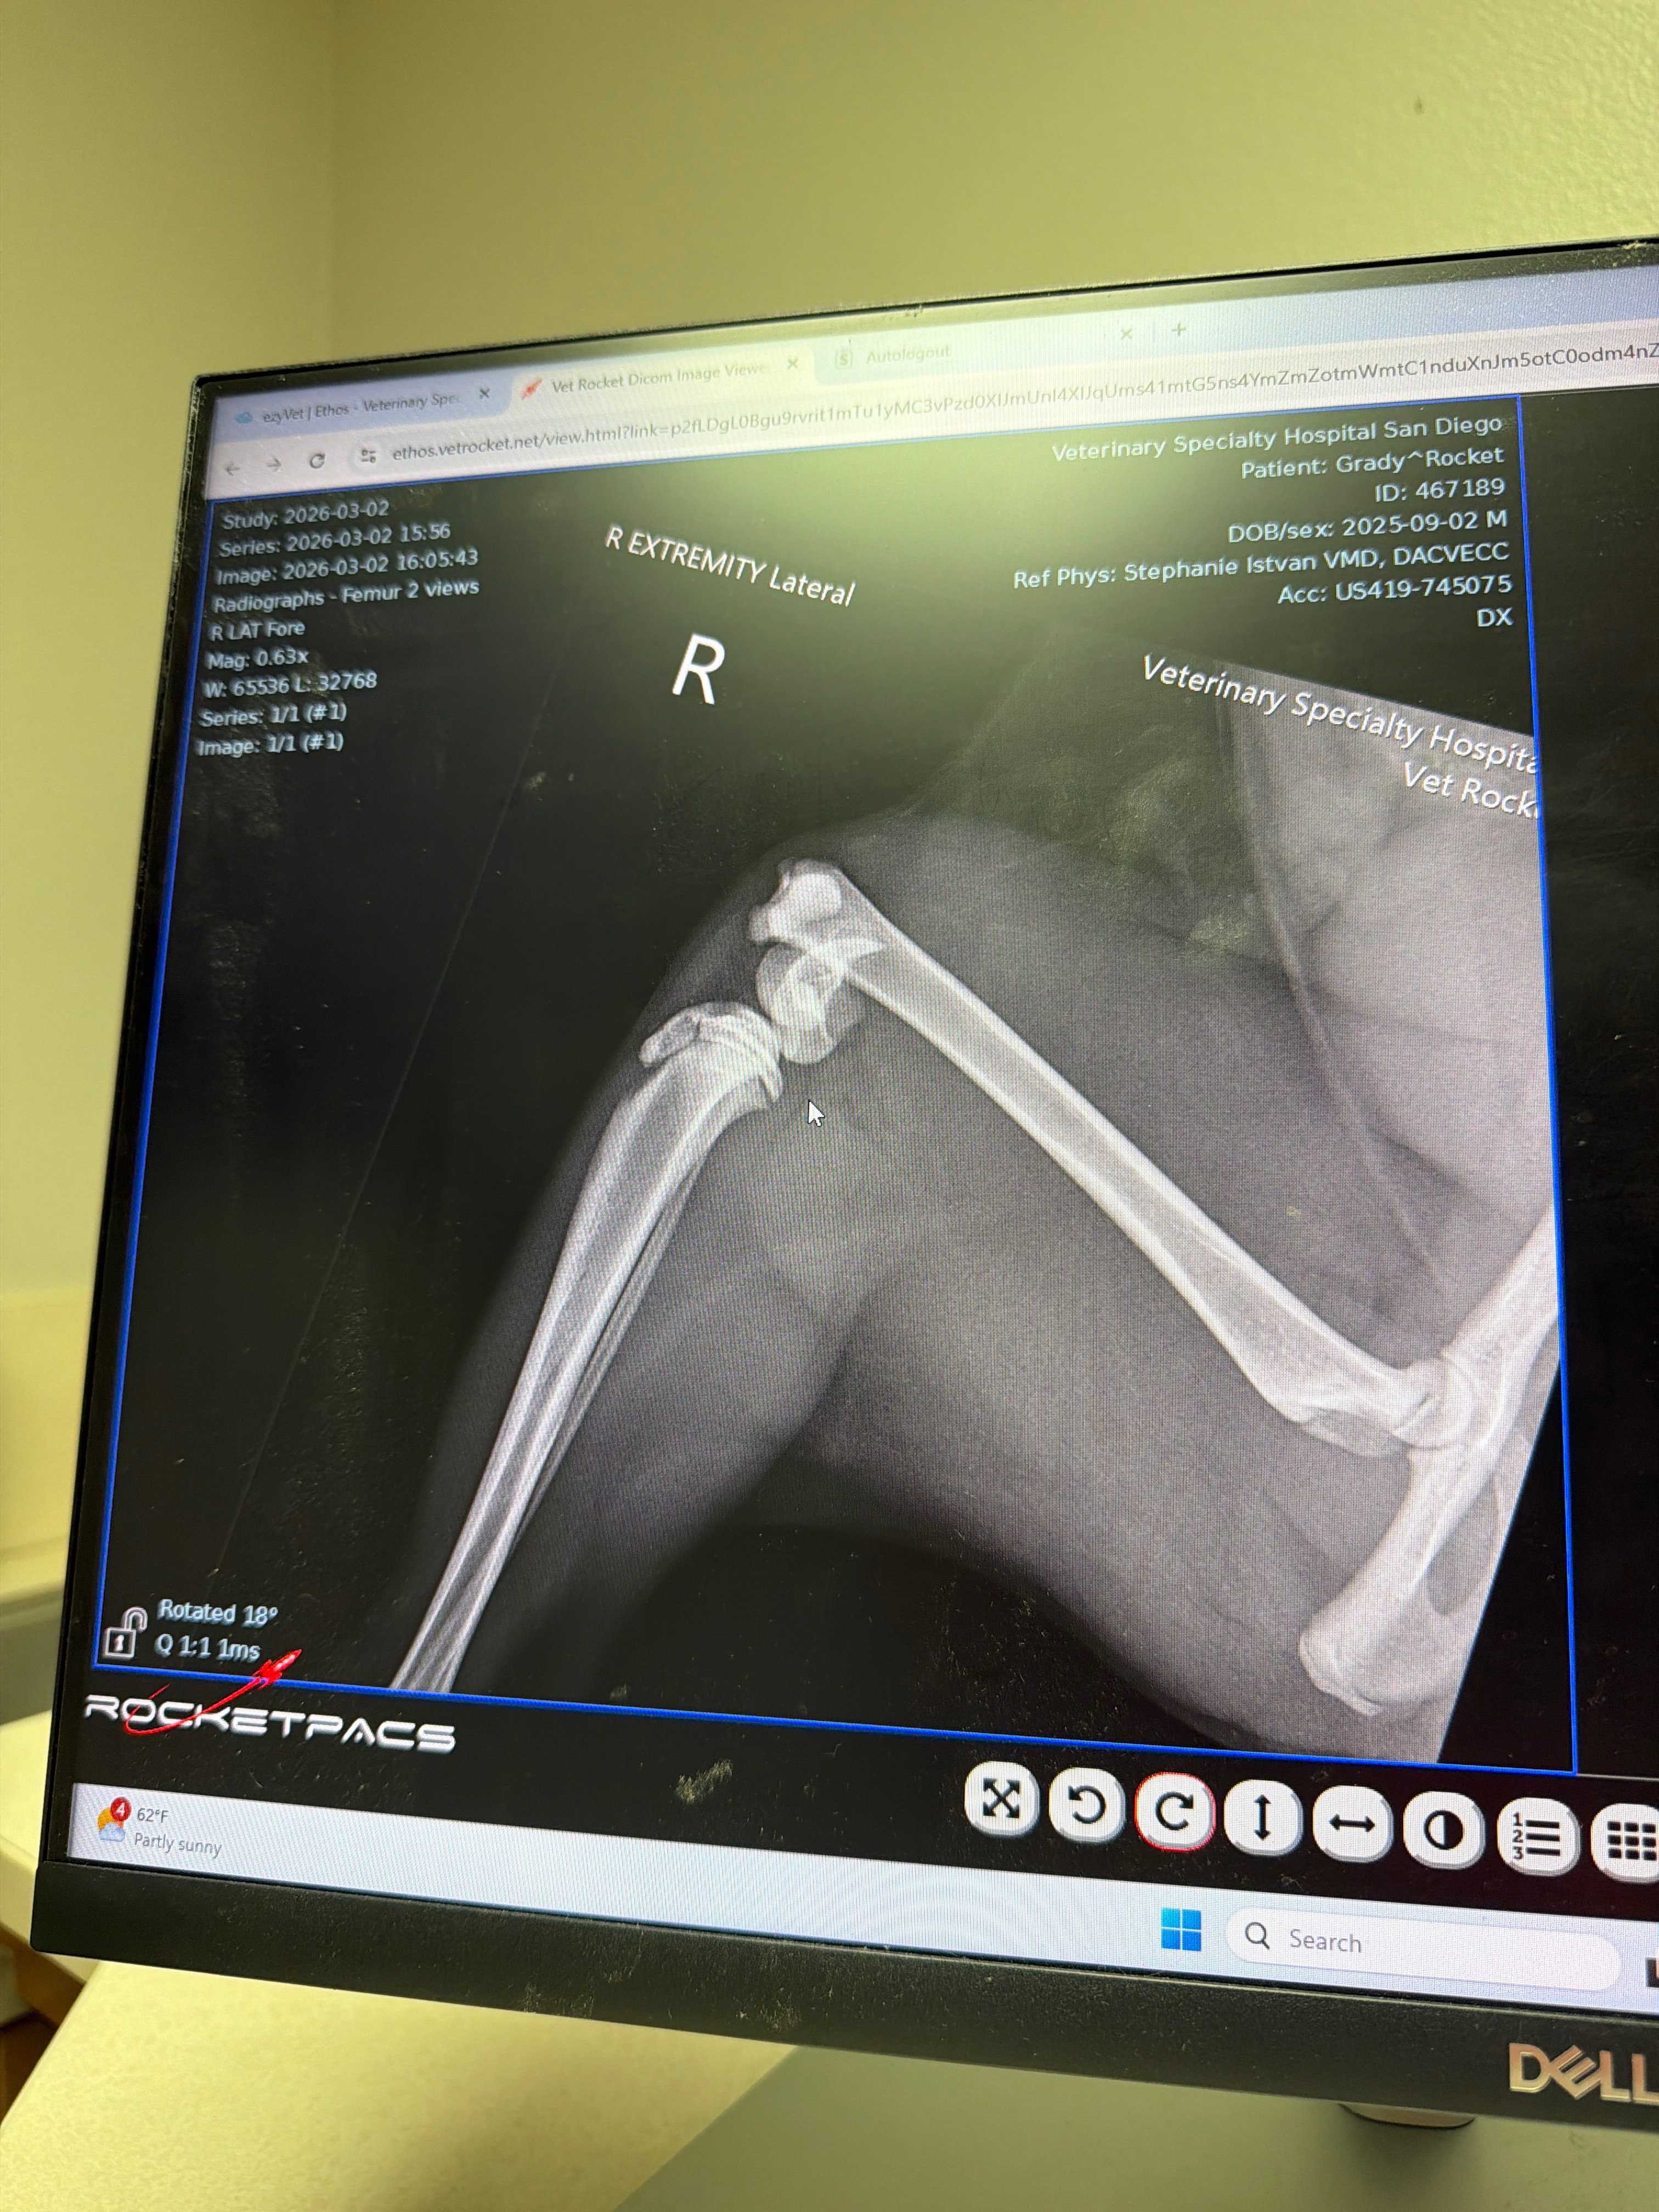

After a full exam and ultrasound, the doctors confirmed that Rocket suffered a complex fracture in his right hind leg near the knee. Thankfully, there were no signs of internal bleeding, but he does have bruising and pain from the fall. Because the fracture is complex and located near a joint, he now needs orthopedic surgery from a specialist to repair his leg so he can walk normally again.